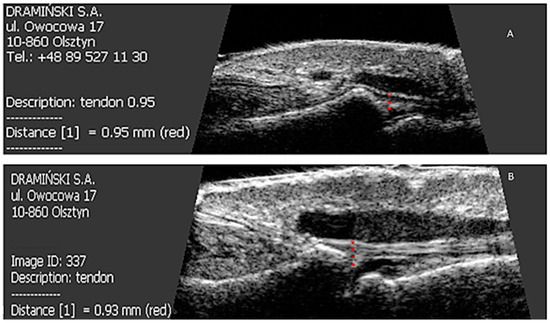

A total of 319 nails were examined: 190 nails in patients with psoriasis without arthritis and 129 nails in patients with PsA. Psoriatic changes in patients with Ps and PsA were present in 145 (76%) and 96 (74%) nails, respectively. Both the extensor tendon (Figure 1) and nail bed (Figure 2) in patients with PsA were thicker than in patients with psoriasis without arthritis (in both cases p < 0.001) and no statistical differences were observed in the thickness of nail plates and nail matrix. The nails with psoriatic changes were assessed in a US examination in regard to their morphology, in accordance with the classification proposed by Wortsman et al. (Figure S2). Focal hyperechoic involvement of the ventral plate (type I), loosening of the borders of the ventral plate (type II) and wavy plates (type III) in patients with psoriasis was observed in 83%, 11.5% and 5.5% of the nails under examination, respectively. No loss of definition of both plates (type IV) was observed. Type I, II, III and IV changes were present in 15.5%, 68%, 7% and 1.5% of the patients with PsA, respectively (Table 2). The digital extensor tendon was the thickest in type II of the changes in US in patients with Ps (p = 0.019), whereas no difference in the thickness of the extensor tendon was found in the group with arthritis depending on the type of changes of nail plates in an US examination. The thickness of the digital extensor tendon did not differ in patients with Ps and with PsA with the onycholysis and hyperkeratosis type changes (concomitant or existing separately), but it was significantly greater than in the pitting-type of changes (p = 0.041 and p = 0.033, respectively). A correlation was found in patients with Ps and PsA between the intensity of clinical changes in nails, as assessed with mNAPSI, with the thickness of the extensor tendon (r = 0.299, p = 0.042 vs. r = 0.336, p = 0.019, respectively). The tendon thickness in patients with Ps correlated with the matrix thickness (r = 0.346, p = 0.023) and the nail bed thickness (r = 0.285, p = 0.034), whereas in patients with PsA, the tendon thickness correlated with the nail bed thickness (r = 0.401, p = 0.011). No relationship between the thickness of the digital extensor tendon in a DIP joint with the intensity of skin changes was observed in either of the groups.

Figure 1. US measurements of tendon thickness in patients studied before and after methotrexate therapy. p < 0.001 Ps before therapy vs. PsA before therapy. p < 0.001 Ps before treatment vs. Ps after six-month therapy. p = 0.61 PsA before therapy vs. PsA after six-month therapy. Ps: psoriasis, PsA: psoriatic arthritis.

All patients were started on methotrexate after the first US examination. After six months of treatment, a decrease in the thickness of nail plates, nail beds and nail matrix was observed in both study groups (Table 4 and Table 5, Figure 3). Methotrexate treatment in the group of patients without arthritis reduced the extensor tendon thickness (Table 4, Figure 1), whereas no such effect was observed in patients with PsA (Table 5, Figure 1 and Figure 4). Methotrexate treatment in both groups reduced the intensity of vascularization as assessed with PD at entheses under study. An intensified PD signal in Ps patients after treatment was observed in 42/190 (22%) nails, like in the PsA group, where it was 29/129 (22.5%) nails.